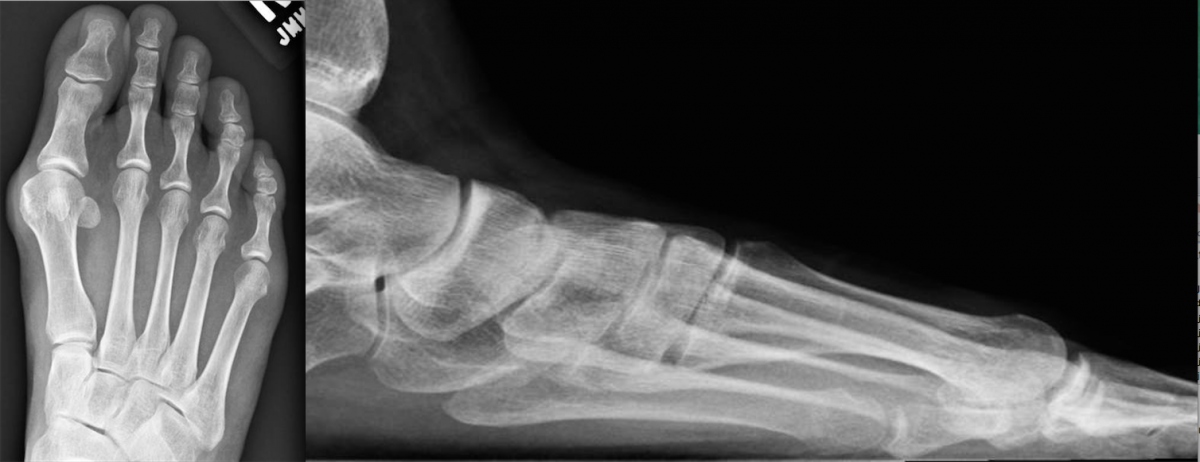

Traditional fixation plates vary in size, shape, thickness and material. However, their primary function remains the same: to provide stability to bone by resisting physiological loads and thereby maintaining anatomic alignment and osseous contact to allow primary bone healing. In general, we can categorize bone plates based on their principal function.

One of the benefits of locking plates is their ability to be “bridge plates,” whereby they provide excellent axial and angular stability, preserve fragmentary blood supply, and reduce the risk of loss of reduction. Indeed, surgeons do not have to contour these plates anatomically to the bone, and the plates have the potential benefit of providing superior fixation in osteoporotic bone. Indications for the use of locking plates include diaphyseal/metaphyseal fractures in osteoporotic bone, multifragmentary diaphyseal/metaphyseal fractures, osteotomies in at-risk patients (poor bone stock, revisions, etc.), articular fractures, segmental fractures with multiple patterns, and any combination of the above.9

Currently, there are no absolute contraindications for locking plates. However, there are instances when applying them may be unnecessary. A good example would be in a case with a simple fracture pattern in a healthy patient with good quality bone.